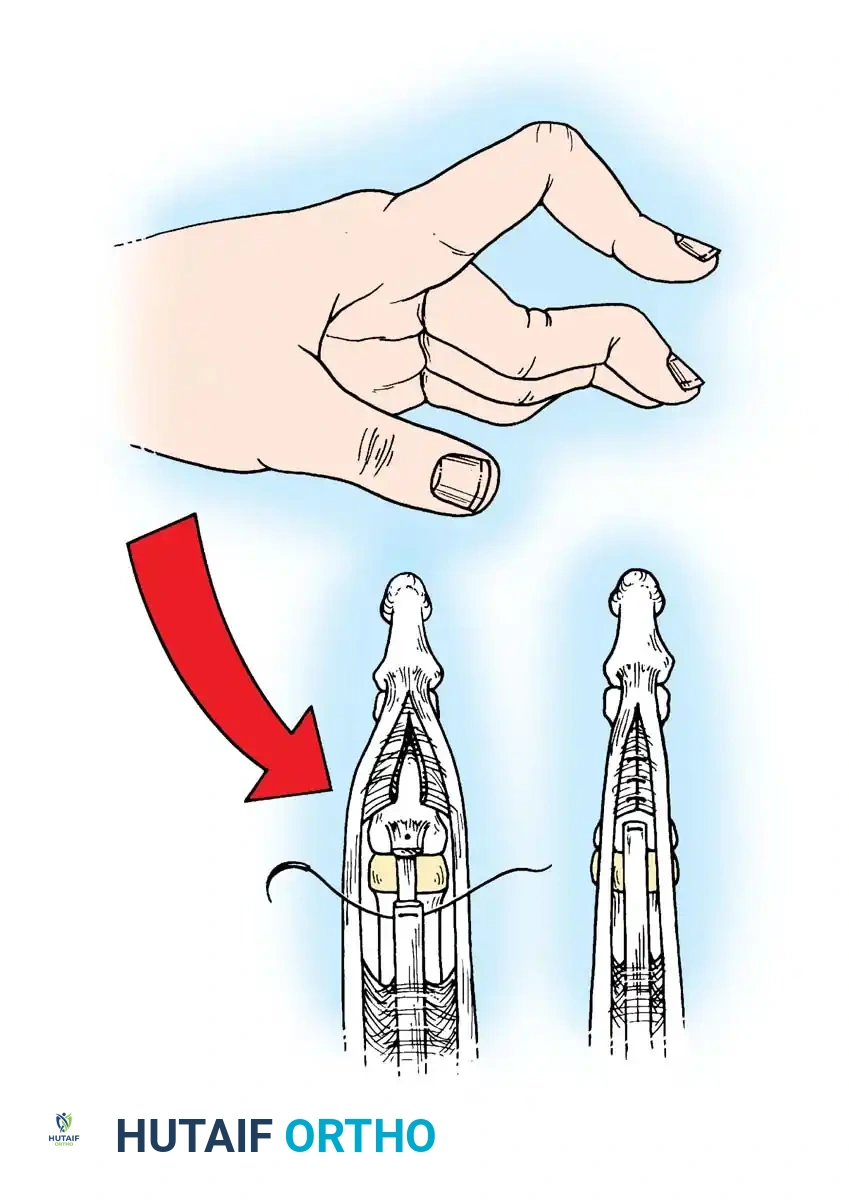

SWAN-NECK DEFORMITY

The swan-neck deformity is defined by a primary hyperextension posture of the PIP joint and a flexion posture of the DIP joint, often accompanied by flexion of the MCP joint. It is driven by profound muscle imbalance and capsular attenuation.

Although classically associated with rheumatoid arthritis, swan-neck deformities also occur in patients with generalized ligamentous laxity (e.g., Ehlers-Danlos syndrome) or post-traumatic conditions. In the rheumatoid hand, the deformity can originate at either the DIP or PIP joint:

- DIP Joint Origin: The deformity may begin as a mallet finger due to attenuation or disruption of the terminal extensor tendon at the DIP joint. This leads to secondary overpull of the central slip, causing hyperextension of a lax PIP joint.

- PIP Joint Origin: Synovitis of the PIP joint causes herniation of the volar capsule and attenuation of the volar plate. This allows the lateral bands and central tendon to subluxate dorsally. Eventually, the lateral bands adhere in a fixed dorsal position, preventing them from sliding volarly over the condyles during PIP flexion.

Nalebuff Classification and Treatment Algorithm

Nalebuff, Feldon, and Millender categorized rheumatoid swan-neck deformities into four distinct types, guiding the surgical approach:

- Type I: Deformities are flexible in all positions.

- Treatment: Dermodesis, flexor tenodesis of the PIP joint, fusion of the DIP joint, or reconstruction of the retinacular ligament.

- Type II: Deformities are characterized by intrinsic muscle tightness (PIP flexion is limited when the MCP is extended).

- Treatment: Intrinsic release combined with Type I procedures.

- Type III: Deformities are stiff and do not allow satisfactory passive PIP flexion, but lack significant radiographic joint destruction.

- Treatment: Joint manipulation, mobilization of the lateral bands, and dorsal skin release.

- Type IV: Deformities exhibit severe stiffness with radiographic evidence of intra-articular destruction.

- Treatment: Arthrodesis of the PIP joint or, in the ring and small fingers, Swanson implant arthroplasty.